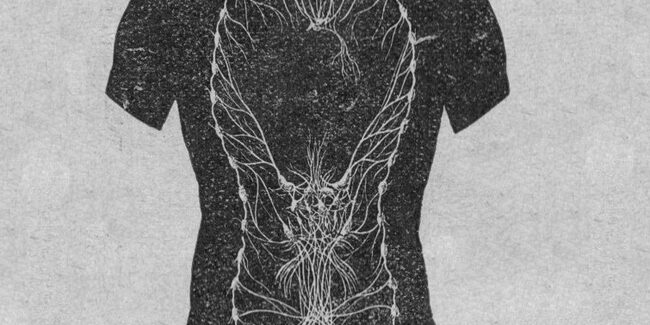

The parasympathetic nervous system, the sympathetic nervous system, and the enteric nervous system comprise the autonomic nervous system in the body. The autonomic nervous system is continuously active and is responsible for unconscious regulation of our glands and organs. The parasympathetic nervous system takes care of “rest and repair” activities, such as salivation, tears, sexual…